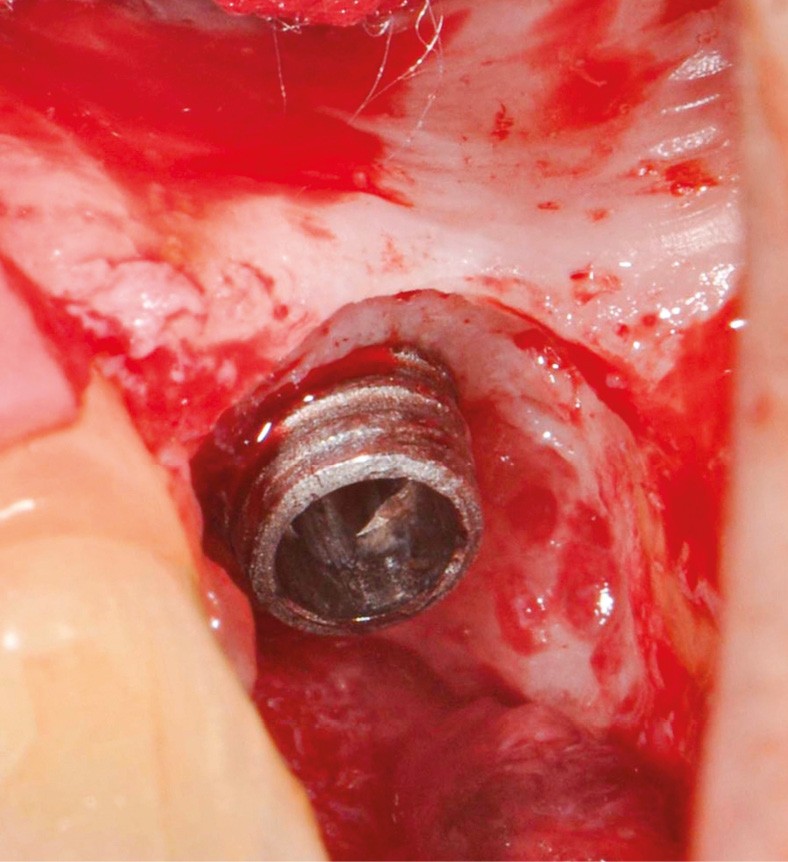

- Péri-implantite diagnostiquée en 2020

Chez cette patiente, le traitement de la péri-implantite a été réalisé à l’aide d’une technique de régénération osseuse guidée péri-implantaire, dont l’indication a été principalement motivée par la morphologie du défaut osseux. Au-delà de la maîtrise du geste chirurgical, le bon résultat obtenu à trois ans est intimement lié à sa coopération en termes de suivi et de contrôle de plaque.